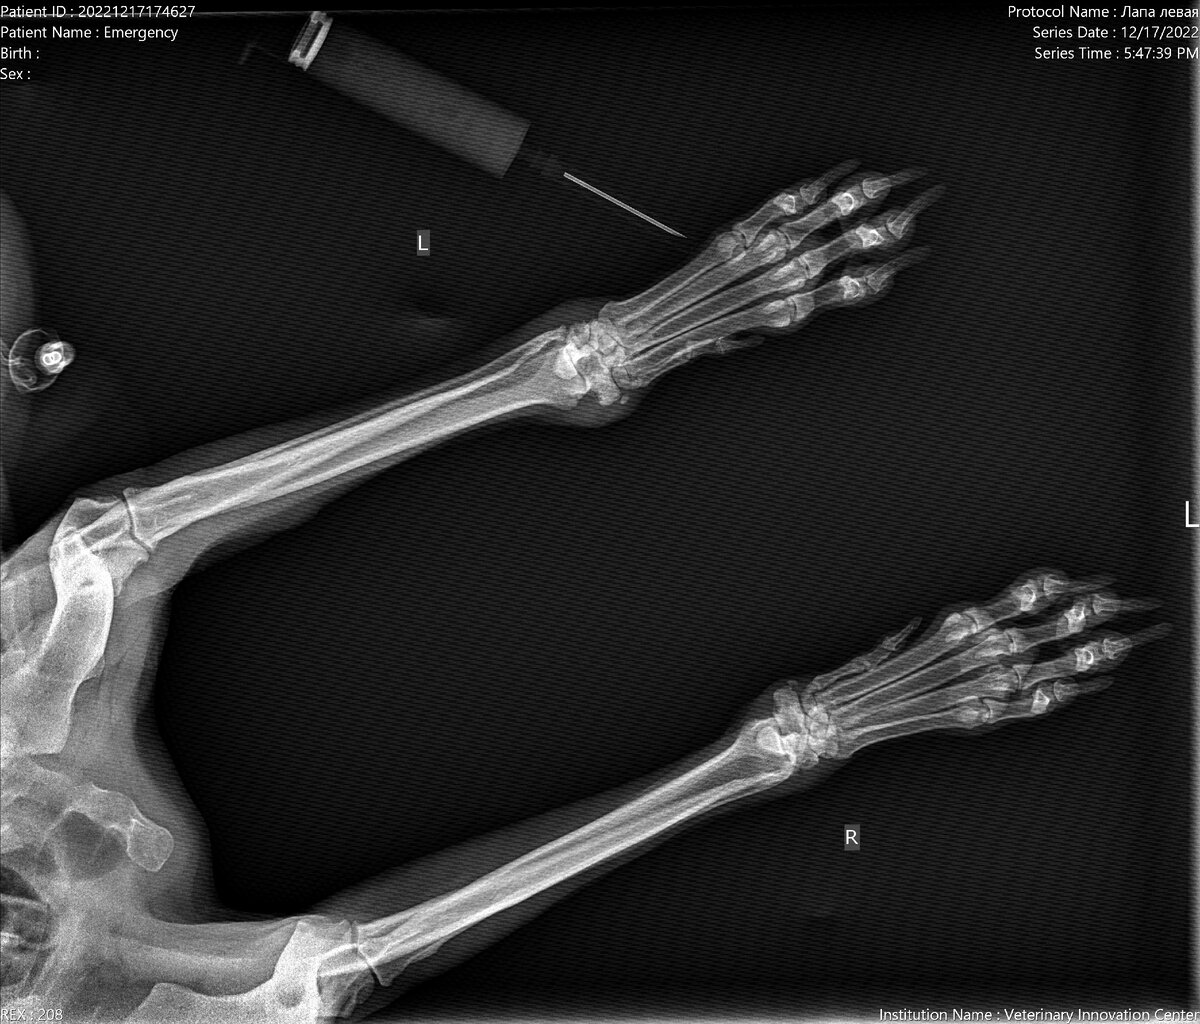

И все было бы замечательно, но с передними лапками у Фионы совсем беда. Последние недели она уже не может ходить нормально, подгибает одну лапку

Лечащий доктор Фионы предположил, что проблема у нее неврологическая. Мы поехали к неврологу, врач рекомендовал МРТ шейно-грудного отдела. Сдали анализы крови, сделали ЭХО сердца и поехали на МРТ. С надеждой ждали заключение. Ведь любой самый жестокий диагноз  лучше, чем полная неизвестность. Но МРТ не дало ответов на наши вопросы. А невролог переменил свое мнение на 180 градусов, после МРТ врач сказал, что со стороны неврологии проблем нет, а нужна консультация травматолога, потому что у Фионы разрушены запястные суставы и требуется операция артродезирования.

UPD 28дек2022: мы проконсультировались с несколькими врачами и все они склоняются к тому, что проблема у Фионы неврологическая. Скорее всего имеет место поражение локтевого или плечевого нерва. Для точного диагноза и назначения лечения нужно КТ локтя и плеча проблемной лапки. Это стоит 19500р. Денег на КТ у нас нет, ведь мы еще не собрали нужную сумму на закупку корма и оплату очередного месяц проживания старичков ******************************************************************************* Прошло 2 месяца, как Фиона покинула приют. Она очень любит свою кроватку, ведь после досчатого пола приютского вольера на матрасике очень сладко спится. А еще соседи по комнате такие душевные, Фионе очень комфортно вместо со Степой и Мирукой. И все было бы замечательно, но с передними лапками у Фионы совсем беда. Последние недели она уже не может ходить нормально, подгибает одну лапку Лечащий доктор Фионы предположил, что проблема у нее неврологическая. Мы поехали к неврологу, врач рекомендовал М